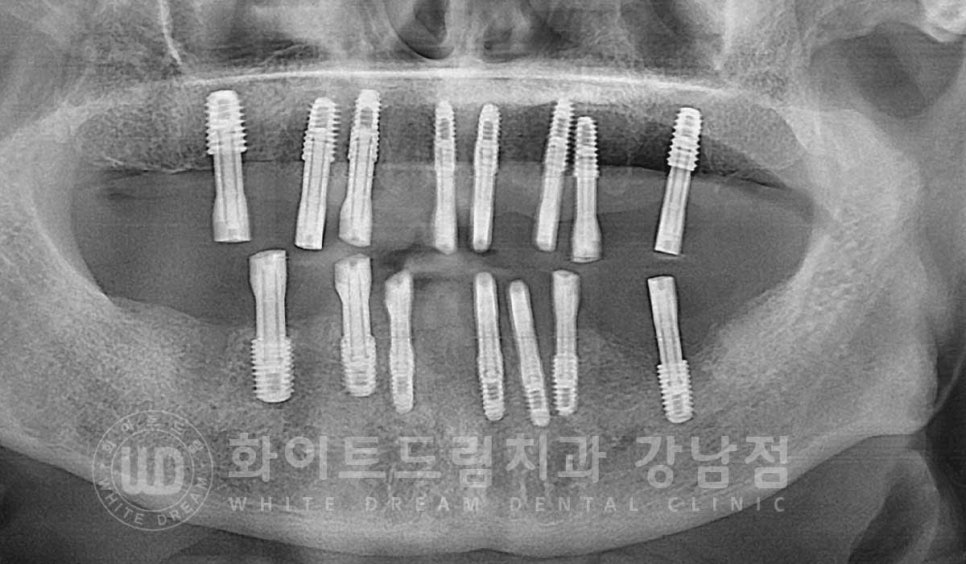

동일 인물이며 동일 환경에서 촬영됨

▲ 전체 임플란트 치료 기간 (약 6개월 소요)

24.04.29 - 24.10.10

환자분의 수술 후 구내 사진입니다.

출혈이 조금 있어 흑백으로 처리를 했는데요.

대부분의 임플란트들은 잇몸뼈의 골 상태가 양호하여

2차 수술(임플란트를 겉으로 노출시키는 수술)까지 진행을 했고

앞서 안내드린 23번 임플란트 수술 부위만 1차 수술(잇몸뼈 안에 임플란트를 식립하는 수술)까지

진행을 하게 되었습니다.

환자분의 치료 전/후 사진입니다.

[동일 인물이며 동일 환경에서 촬영되었습니다.]

기간 : 24.04.29 - 24.10.10